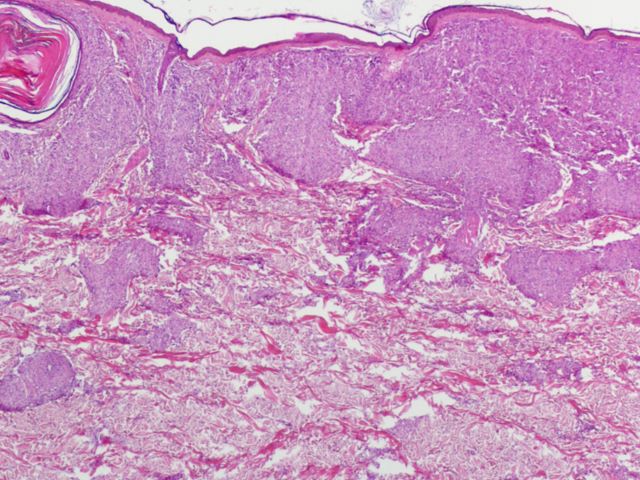

370 -- pb260096.jpg